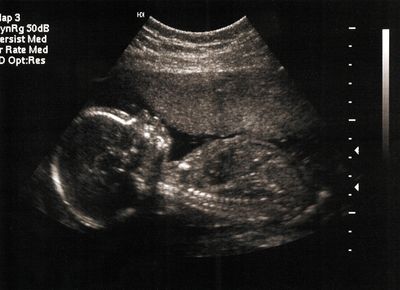

Ultrasound, also known as sonography, is a safe, painless, and non-invasive imaging technique that uses high-frequency sound waves to create live images of the inside of the body.